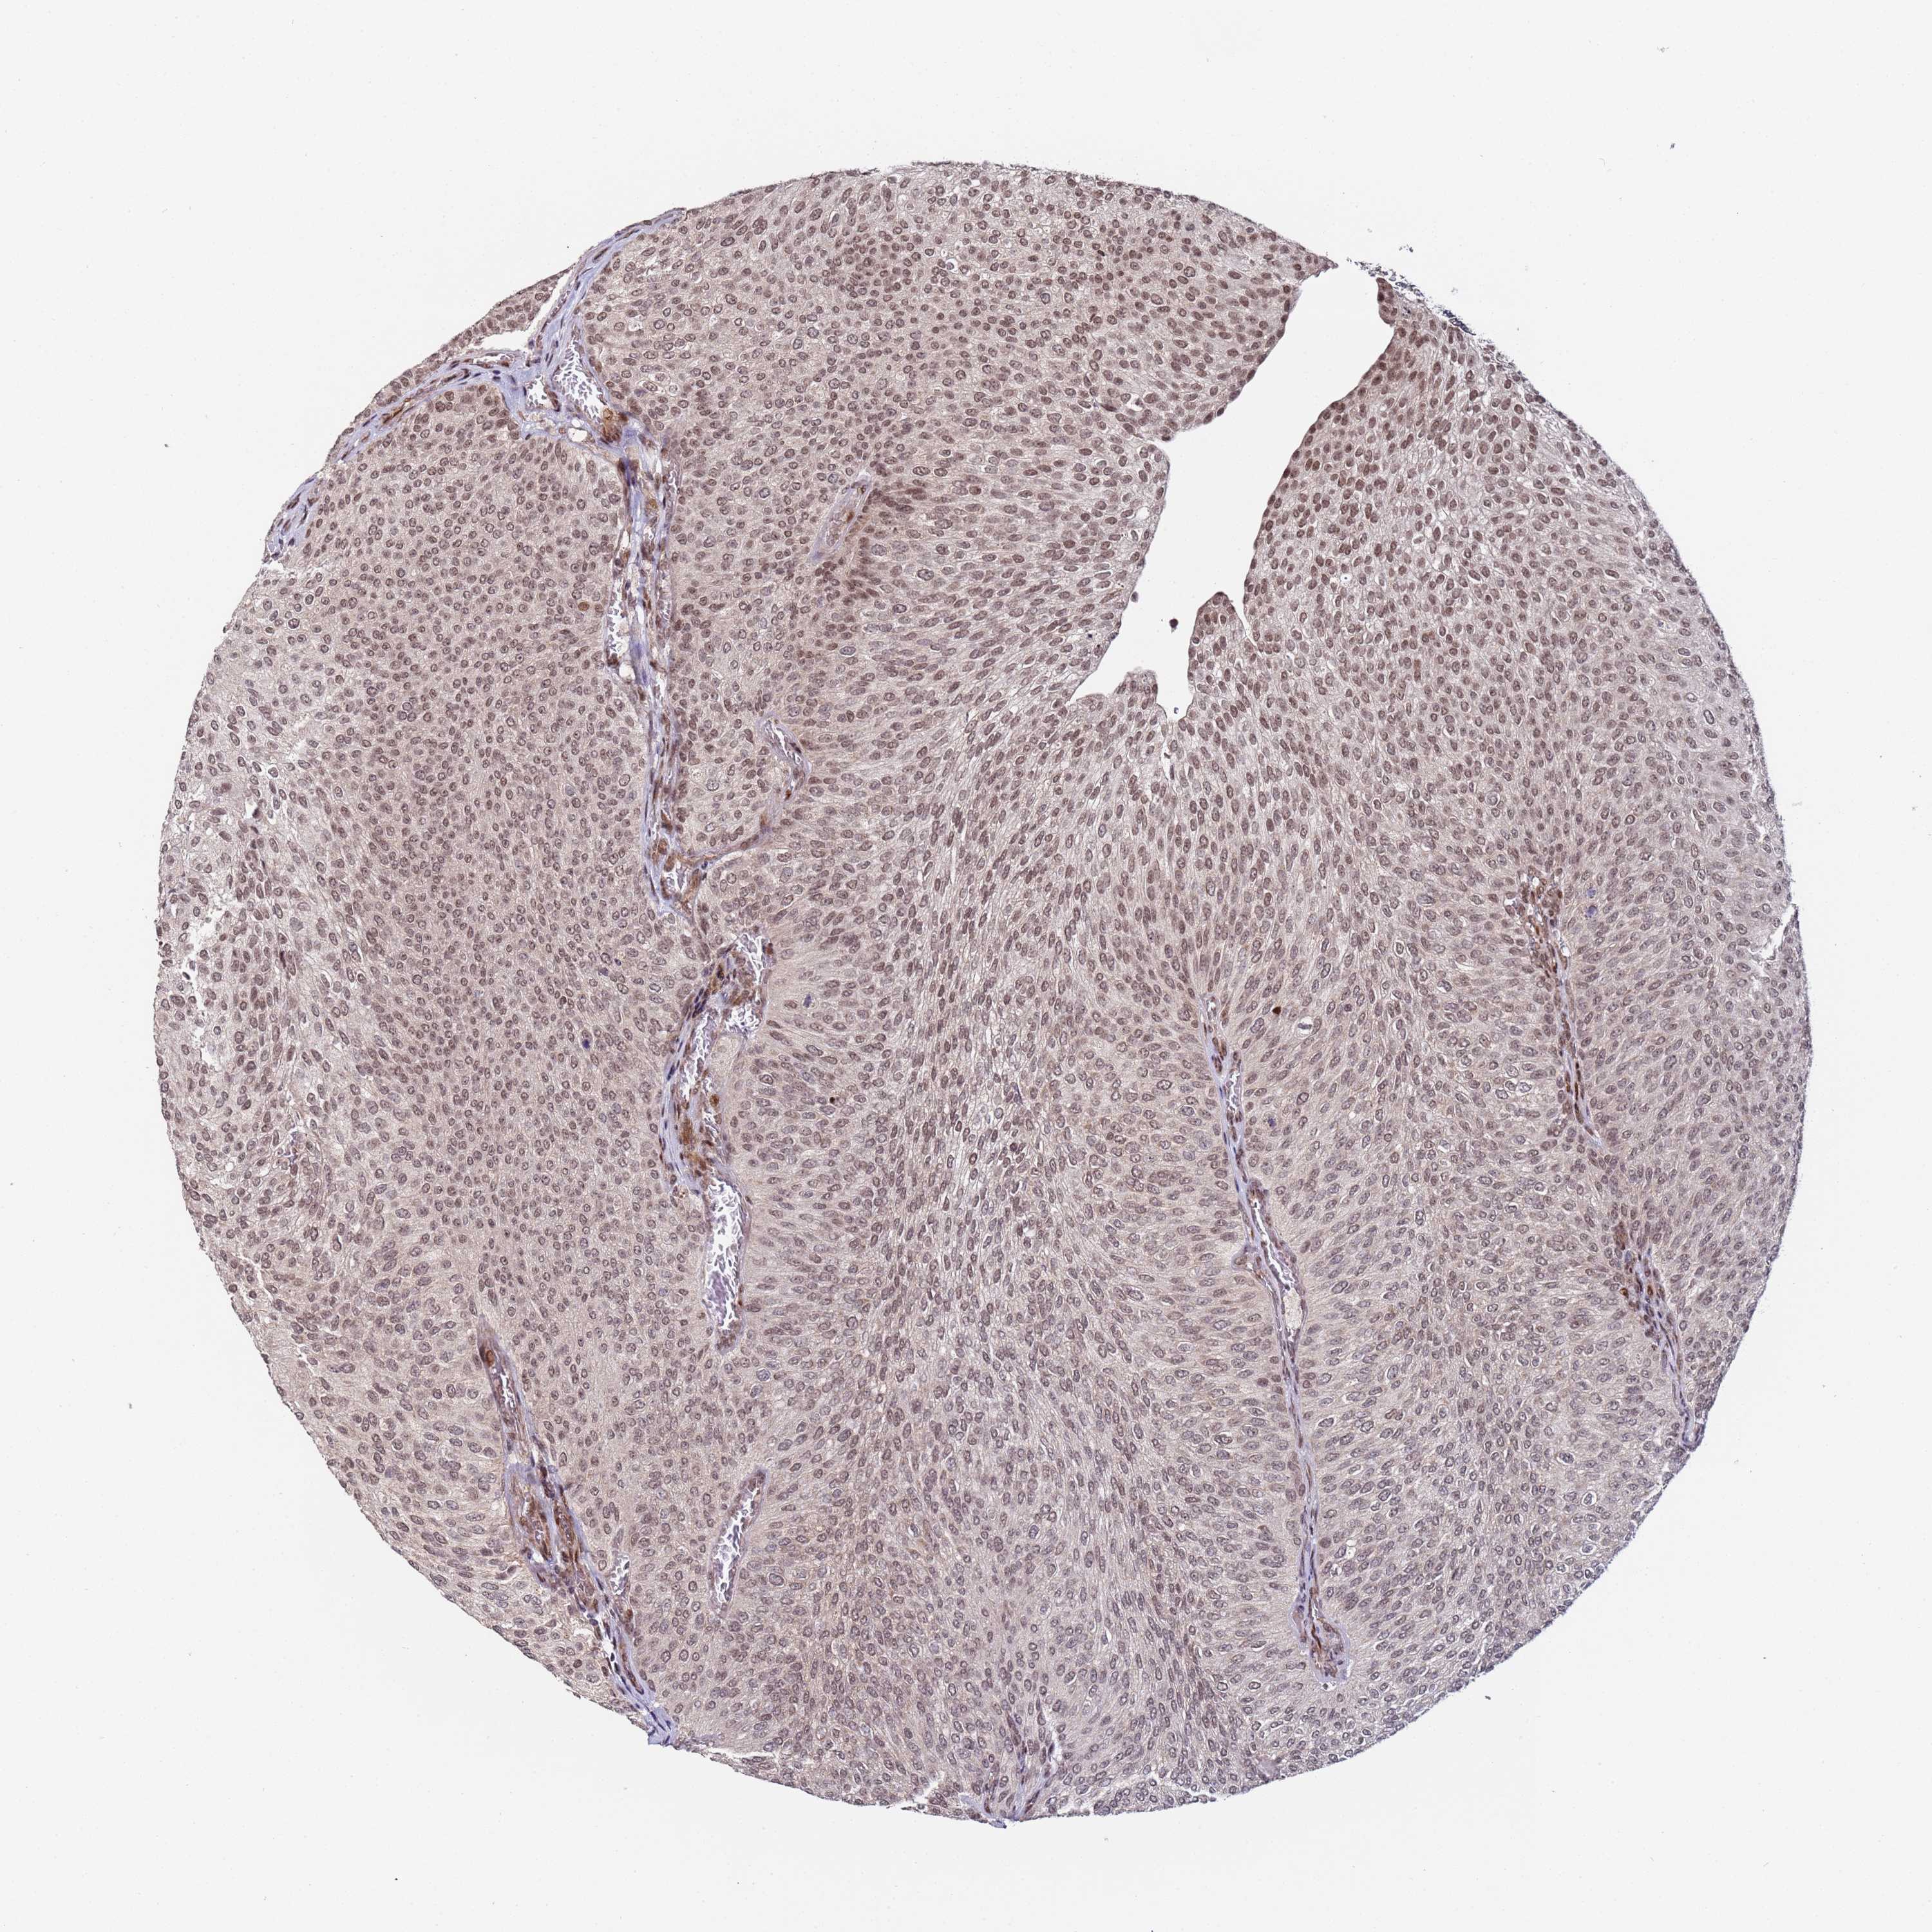

UROTHELIAL CANCER - Protein expressioni

A mouse-over function shows sample information and annotation data. Click on an image to view it in a full screen mode. Samples can be filtered based on level of antibody staining by selecting one or several of the following categories: high, medium, low and not detected. The assay and annotation is described here.

Note that samples used for immunohistochemistry by the Human Protein Atlas do not correspond to samples in the TCGA dataset.

Antibody stainingi

Antibody staining in the annotated cell types in the current human tissue is reported as not detected, low, medium, or high, based on conventional immunohistochemistry profiling in selected tissues. This score is based on the combination of the staining intensity and fraction of stained cells.

Each image is clickable and will lead to virtual microscopy that enables deeper exploration of all samples and also displays staining intensity scores, fraction scores and subcellular localization as well as patient and tissue information for each sample.

Antibody HPA044244

Antibody HPA058777

Antibody CAB020694

Staining

High

Medium

Low

Not detected

Intensity

Strong

Moderate

Weak

Negative

Quantity

>75%

75%-25%

<25%

None

Location

Nuclear

Cytoplasmic/membranous

Cytoplasmic/membranous,nuclear

Urothelial carcinoma, High grade

Urothelial carcinoma, Low grade

Urothelial carcinoma, NOS